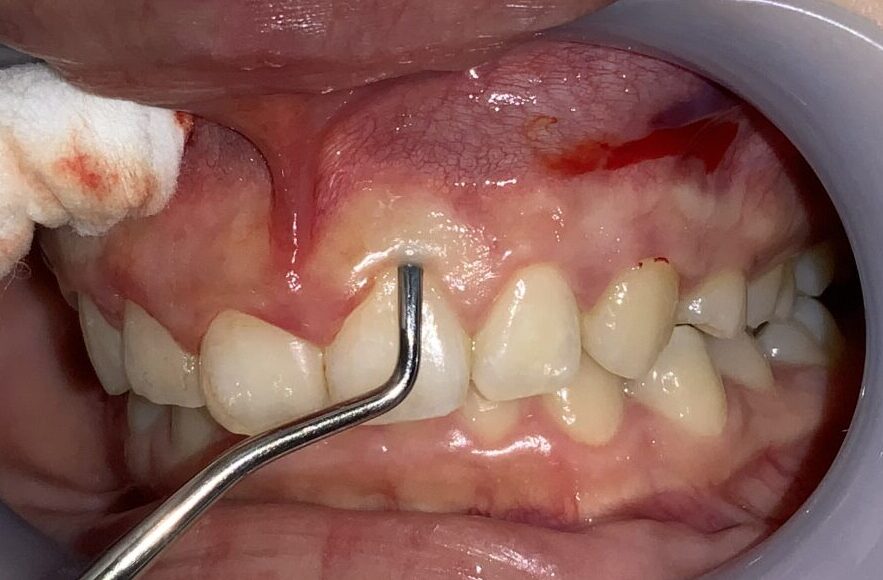

最後に犬歯の検査をします。

犬歯もこのように小さな形ではなく、綺麗な形になります。

八重歯にならないように細心の注意をします。

今回の患者様のご希望の本数は6本でしたので、検査は終了しました。治療の本数は患者様のご希望に合わせております。本数が増えても追加の費用はありません。